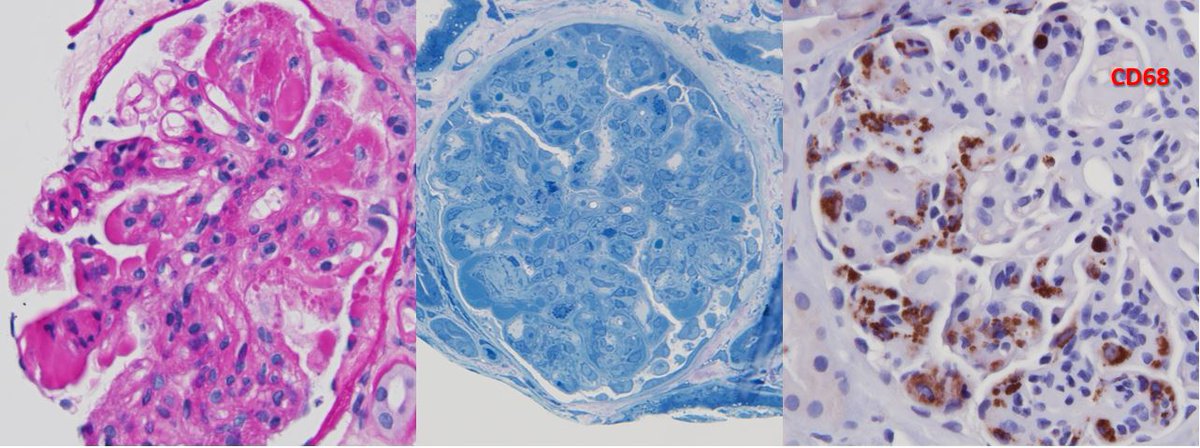

Crazy Cryo: 63 yo M w/ DM, syphilis, untreated (severe) HCV infection, bx/ed for proteinuria. Positive cryo's, SPEP with IgM-kappa paraprotein. Gloms with nodules, GBM double contours, macrophages, and intracapillary cryo aggregates. Classic EM findings. Yup, it STILL happens!

Classic example! Thanks, @JeanHouMD